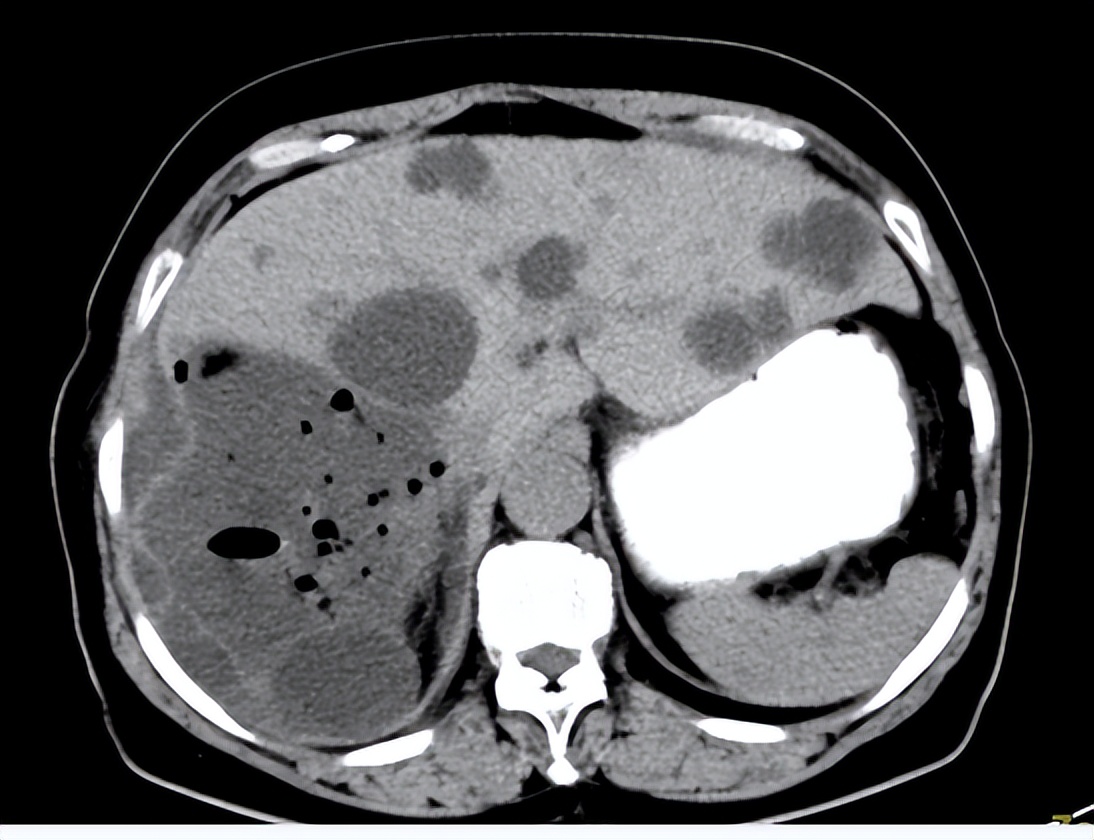

CT:肝内多发特大囊肿

CT:单个最大者>15cm

患者女性,50岁,多年前健康查体发现多发肝囊肿,最大者直径4cm。一年来感觉右上腹胀满,疼痛,食欲减退,来院检查,CT/超声提示:肝内多发肝囊肿,最大者直径>15cm。患者住院行:介入超声肝囊肿硬化治疗术。

术后48小时复查CT:原较大囊肿位置内见多发气体影,邻近肝包膜内陷,肝周见少量水样密度影。

术后CT